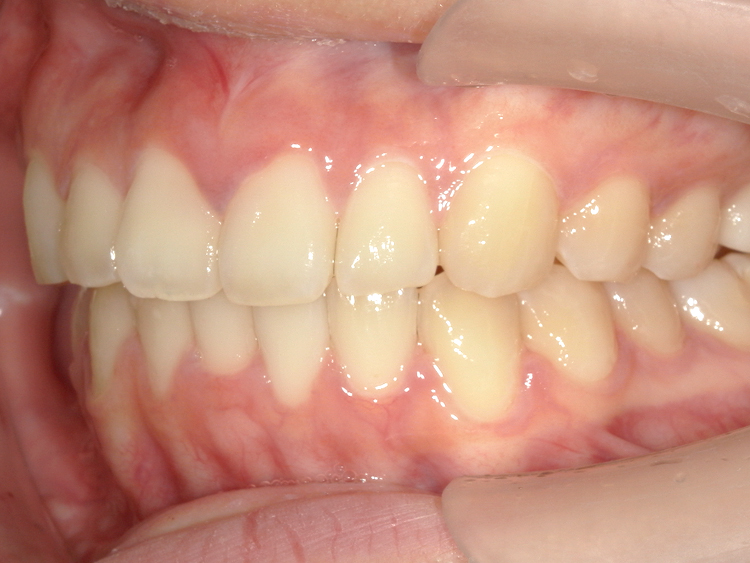

症例1

Before

After

| 主訴 | 上前歯の突出を治したい (出っ歯を治したい) |

|---|---|

| 年齢 | --- |

| 治療期間 | 約5ヶ月 |

| 治療内容 | インビザラインiGoで上顎のみ治療。 前歯の歯と歯の間をごく少量削り、 前に出ている歯が入るスペースを作り、綺麗に揃えた。 |

| 治療費 | ¥352,000(税込)+月額調整料 |

| 治療のリスク | 歯と歯の間を削ることでスペースを確保するので、 場合によっては歯が染みる症状が出ることがある。 |